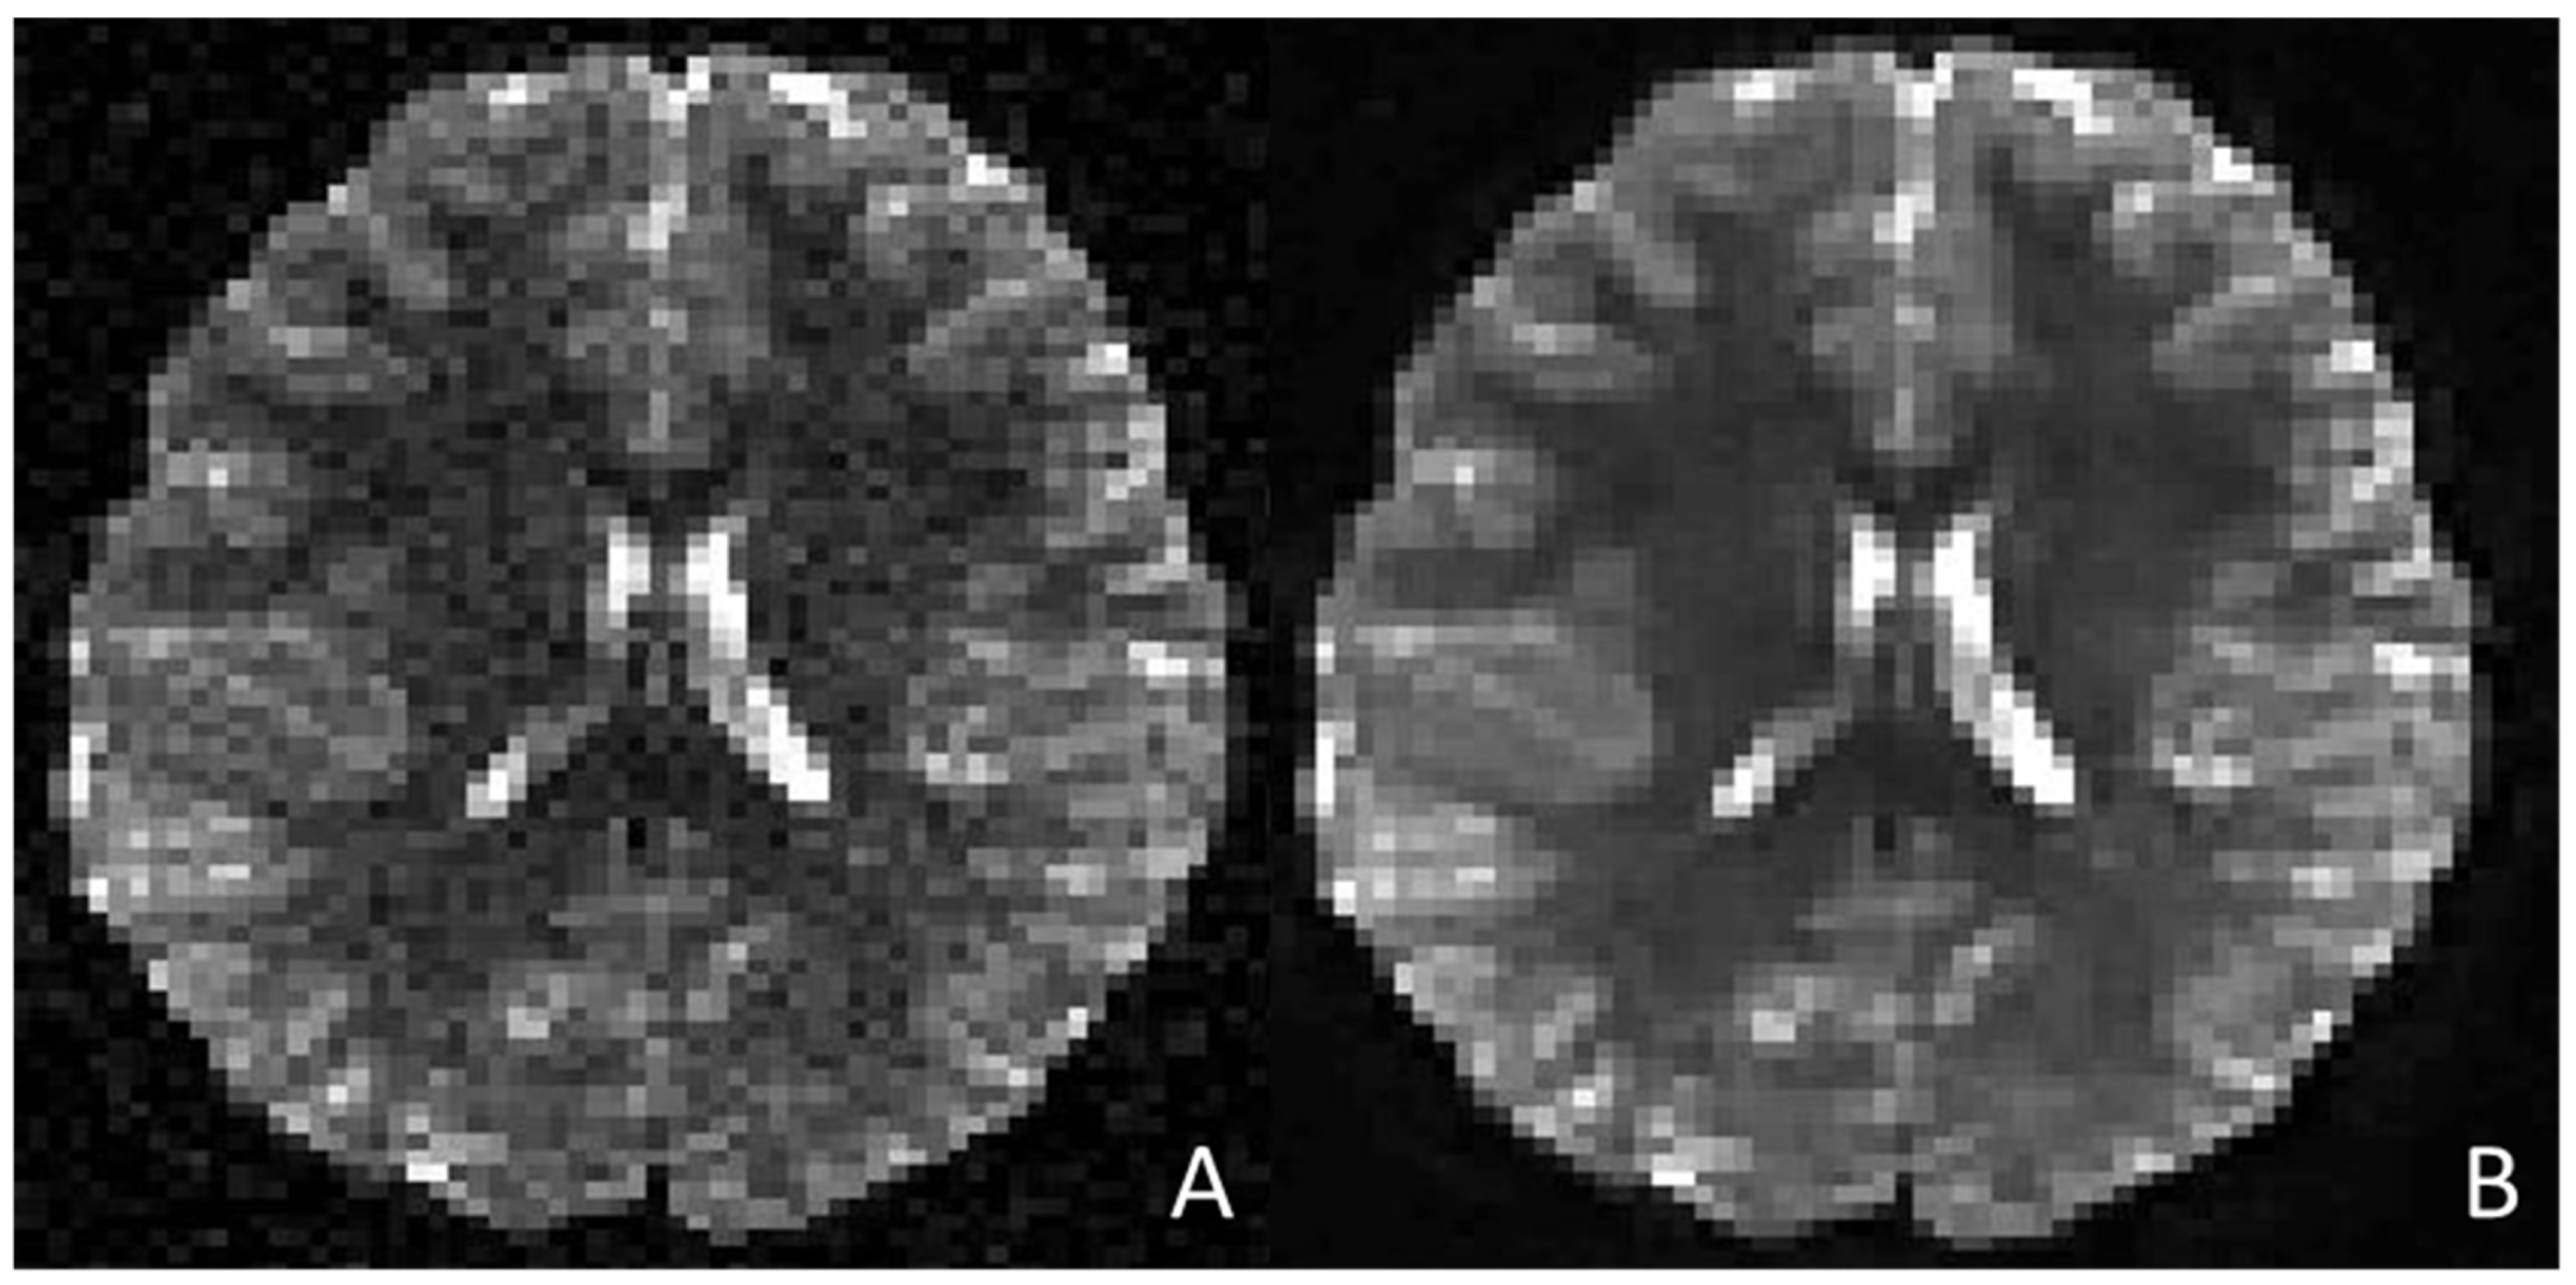

- Zhang, S.; Zhong, M.; Shenliu, H.; Wang, N.; Hu, S.; Lu, X.; Lin, L.; Zhang, H.; Zhao, Y.; Yang, C.; et al. Deep Learning-Based Super-Resolution Reconstruction on Undersampled Brain Diffusion-Weighted MRI for Infarction Stroke: A Comparison to Conventional Iterative Reconstruction. AJNR Am. J. Neuroradiol. 2025, 46, 41–48. [Google Scholar] [CrossRef]

- Matsuo, K.; Nakaura, T.; Morita, K.; Uetani, H.; Nagayama, Y.; Kidoh, M.; Hokamura, M.; Yamashita, Y.; Shinoda, K.; Ueda, M.; et al. Feasibility Study of Super-Resolution Deep Learning-Based Reconstruction Using K-Space Data in Brain Diffusion-Weighted Images. Neuroradiology 2023, 65, 1619–1629. [Google Scholar] [CrossRef]